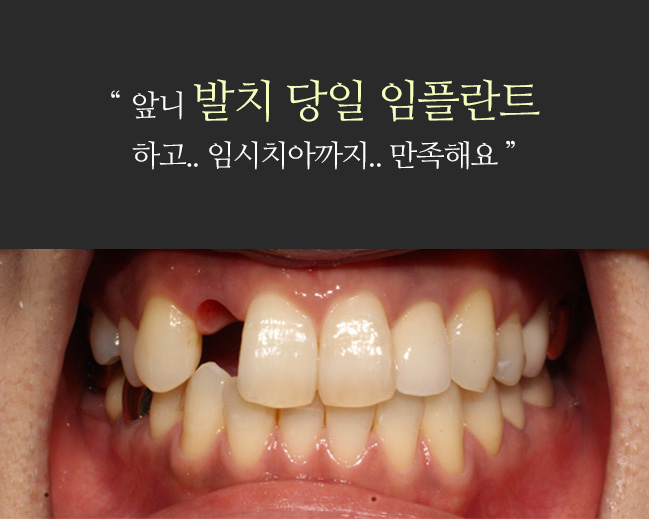

implant 임플란트

실패할 임프란트는 심지 않겠습니다.

미소드림의 임플란트 환자는 95% 소개 환자입니다.